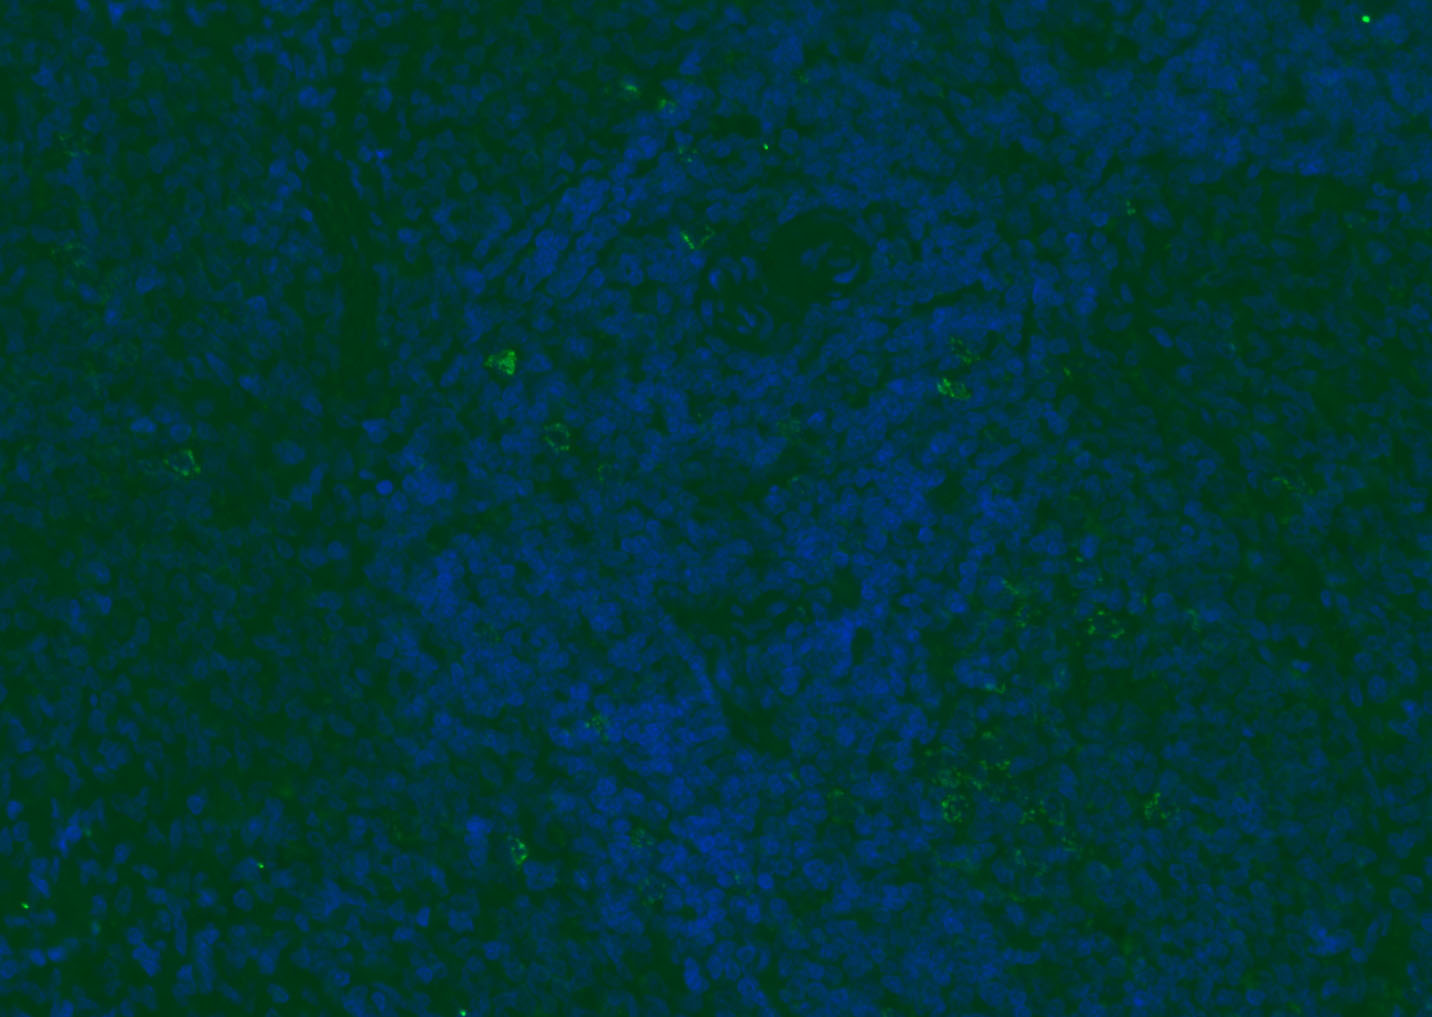

Paraformaldehyde-fixed, paraffin embedded (mouse lymphoid); Antigen retrieval by boiling in sodium citrate buffer (pH6.0) for 15min; Blocking buffer (normal goat serum) at 37°C for 30min; Antibody incubation with (CD8B) Polyclonal Antibody, Unconjugated (bs-4914R) at 1:200 overnight at 4°C, followed by a conjugated Goat Anti-Rabbit IgG antibody (bs-0295G-FITC) for 90 minutes, and DAPI for nuclei staining.